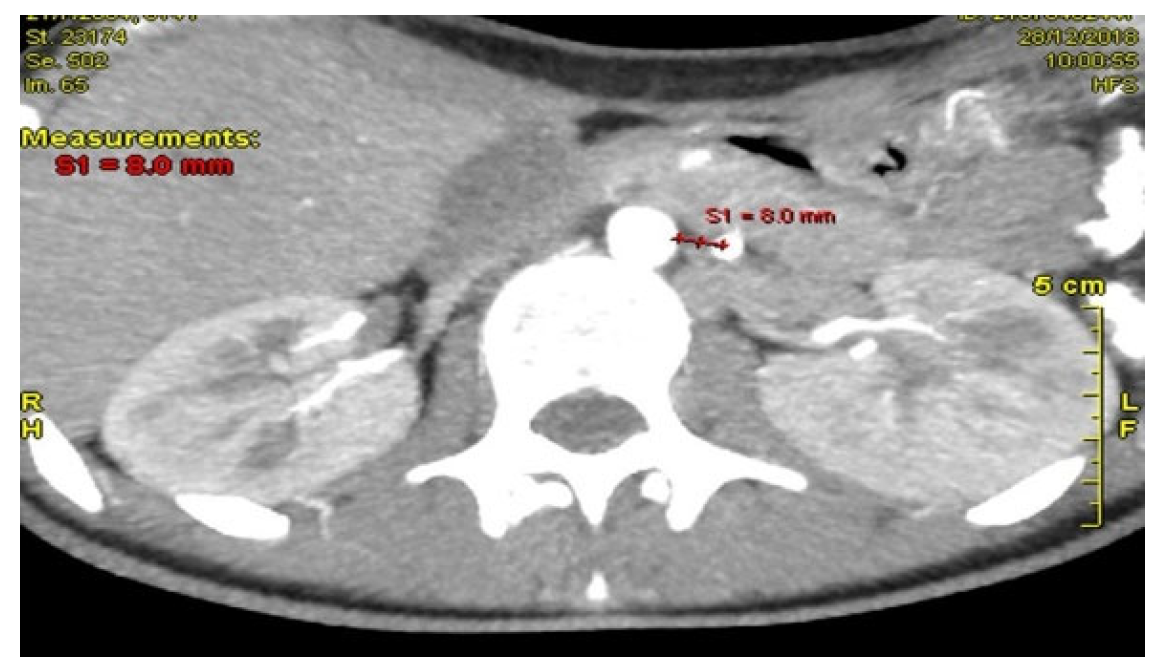

Computed Tomography Angiography (CTA) Figure 2, provided definitive anatomical correlation. At the level where the third portion of the duodenum crosses between the abdominal aorta and the SMA, the aortomesenteric angle was significantly reduced to 6° (normal: 38–56°), Figure 3 and the aortomesenteric distance measured 4 mm (normal: >10 mm, with <8 mm considered pathological). Figure 4 These findings were consistent with SMAS, a rare condition caused by vascular compression of the third portion of the duodenum between the SMA and the aorta.

Figure 2. CTA: The aortomesenteric angle was significantly reduced to 6°.